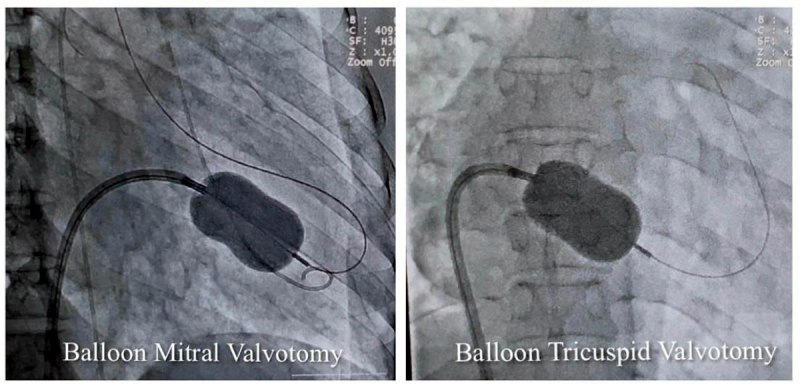

कार्डियोलॉजी विभाग के हृदय रोग विशेषज्ञ और ऐसोसिएट प्रोफेसर डॉ. शिशिर सोनी ने बताया कि मरीज को अत्यधिक गम्भीर अवस्था में सुपर स्पेशलिटी अस्पताल लाया गया था। इससे पहले उसे महाकोशल के कई अस्पतालों और नागपुर के हृदय रोग विशेषज्ञों को दिखाया जा चुका था, लेकिन इलाज नहीं हो सका। डॉ. सोनी ने बताया कि मरीज के मिट्रल और ट्राइकसपिड दोनों वॉल्व में स्टेनोसिस (सिकुडऩ) थी। इस बीमारी में मरीज को अत्यधिक सांस फूलने और पैरों में सूजन की समस्या होती है। इसके अलावा अन्य समस्याएं धडकऩों की अनियमितता, कम बीपी और फेफडें, पेट और अन्य जगहों में पानी भर जाने जैसी परेशानियां भी थीं। उन्होंने बैलून तकनीक से एक ही बार में परक्यूटेनियस मिट्रल और ट्राइकसपिड बैलून वाल्यूलोप्लास्टी सफलतापूर्वक की। इलाज के बाद महिला को पूर्णत: लाभ मिला है।

डॉ. शिशिर सोनी ने बताया कि एक ही मरीज में दोनों वॉल्व की सिकुड़न का परक्यूटेनियस मिट्रल और ट्राइकसपिड बैलून पाल्यूलोप्लास्टी से सफलतम उपचार दुनिया के कुछ ही कार्डियेक सेंटर में हुआ है। मध्यप्रदेश में यह उपचार पहली बार किया गया है।